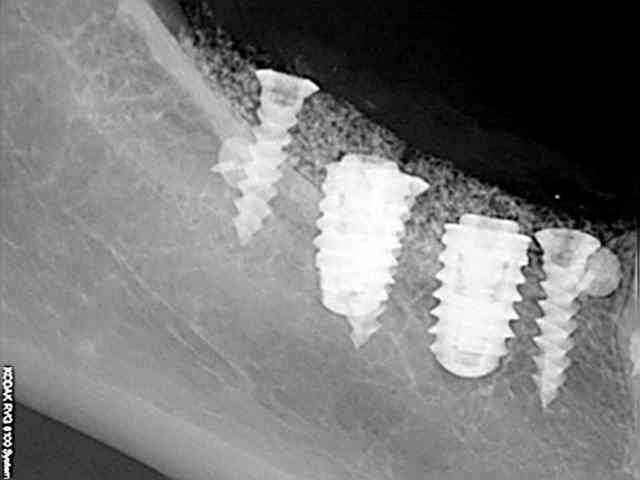

Comme dans la radio de contrôle 1 que tu viens d'envoyer.( qui apparemment est une radio faite juste après ton intervention)

je me dis aussi, à la vu des coupes, que tu repères le V3 trop haut?

dommage qu'on ne les voit qu'en petit.

J'ai parfois des problèmes pour repérer le V3 sur des coupes de conebeam (Vatech, que je fais faire à un copain). Ma pano m'aide pour mieux le repérer (Kodak). Tu n'aurais pas de "vrai" pano pour comparer?